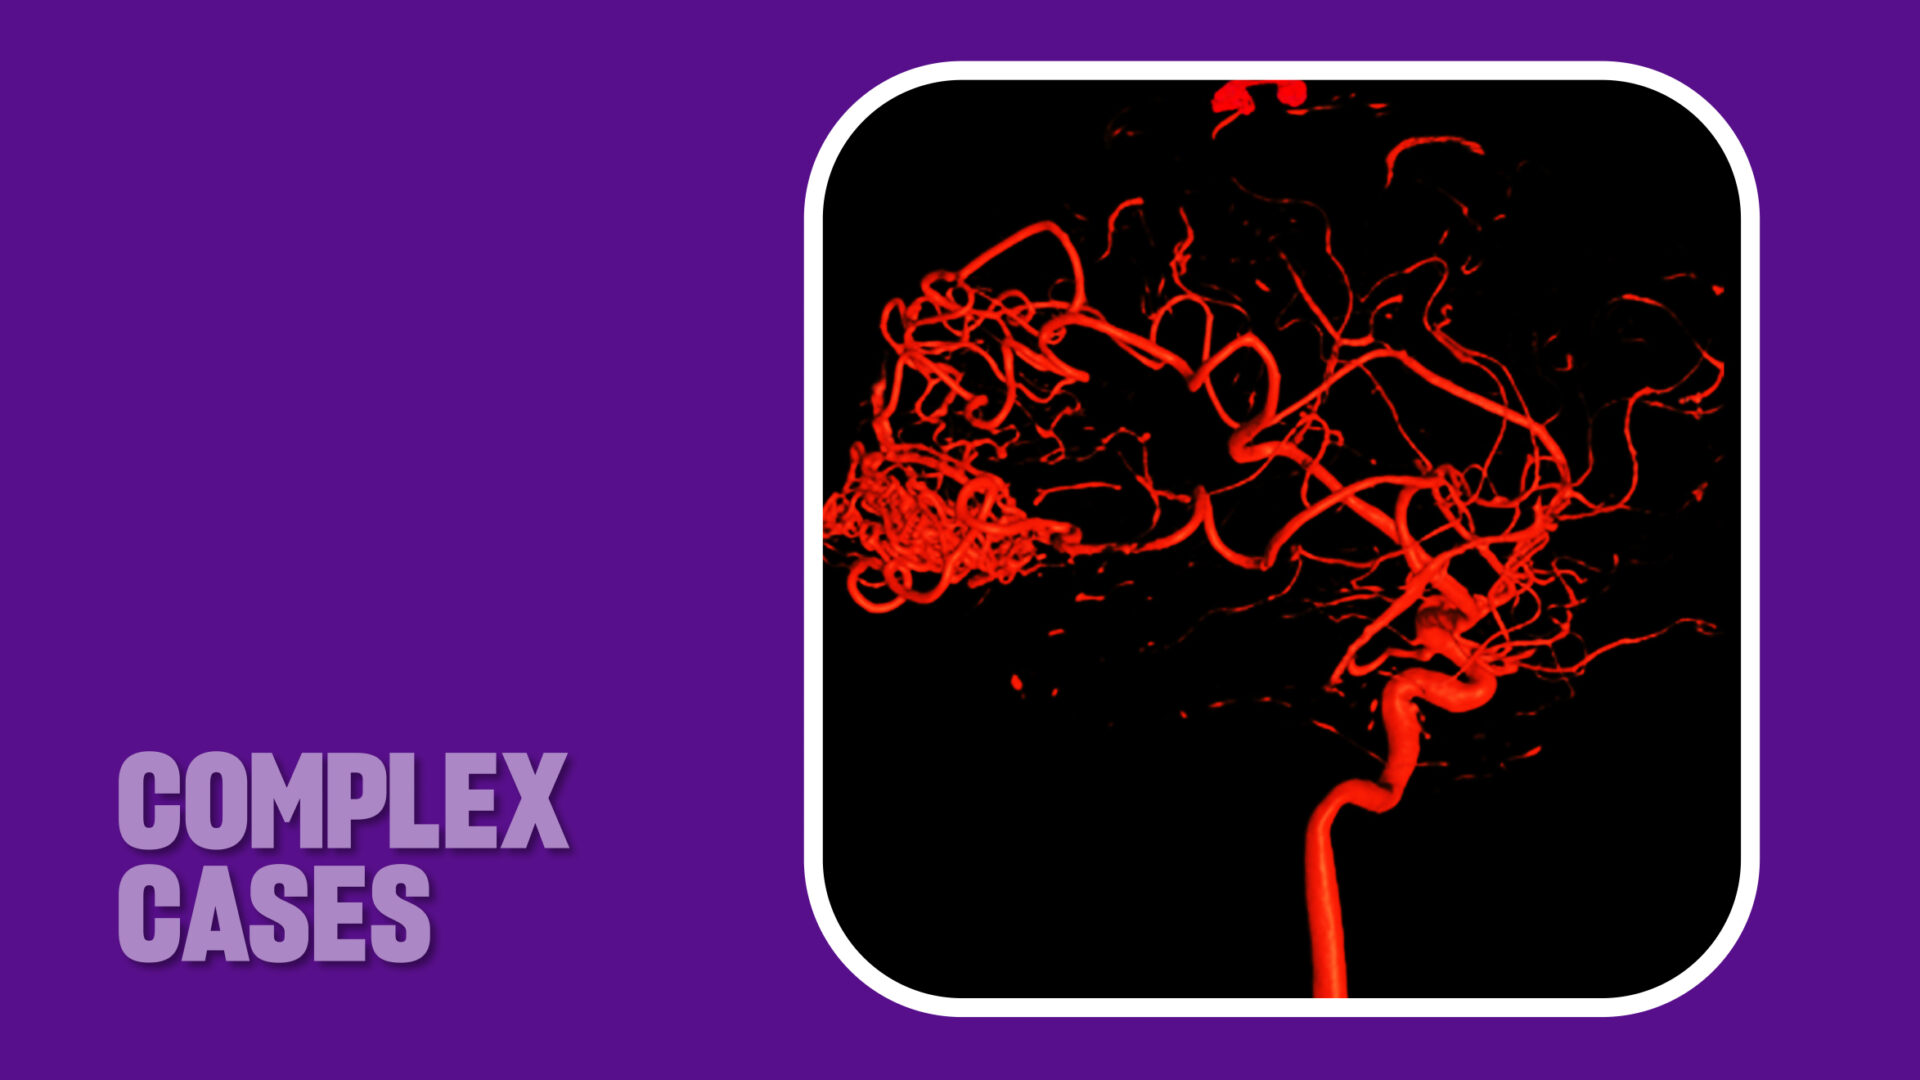

- Preoperative angiography with 3D reconstructions revealed the AVM to be 4 cm in size and at a high risk of bleeding.

Dr. Riina initially performed diagnostic and rotational angiography with 3D reconstructions (Slide 1) to better characterize the vascular pathology and to inform clinical decision-making. The detailed imaging confirmed the exact size and location of the AVM, as well as the arterial branches feeding it. The imaging also revealed several areas of the lesion featuring a high risk for potential bleeding.